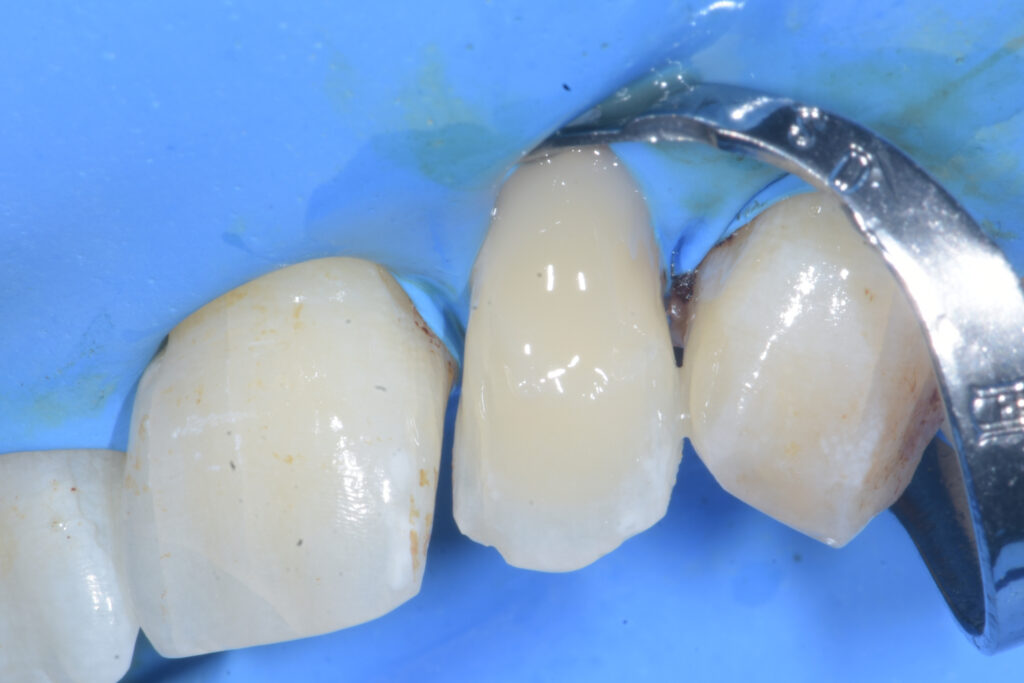

Effettuata l’adesione si procede con il posizionamento di circa 0,5mm di Venus Flow (Kultzer) seguiti da una stratificazione mediante il composito Enamel Plus Hri (Micerium) (Figura 5).

Rimossa la diga, si procede con la lucidatura del complesso restauro-dente mediante frese carborundum e gommini di durezza decrescente. Viene eseguita la radiografia intraoperatoria a lembo aperto (Figura 6).